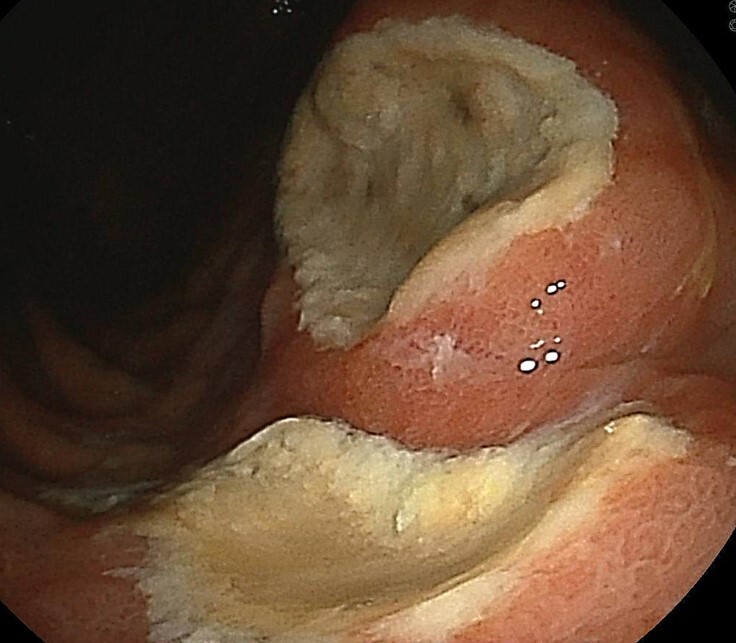

当院検査で見つかった胃潰瘍、腰痛に対する痛み止め内服によるもの

早期で発見された胃癌、他院で内視鏡治療を行い根治

進行胃癌、外科手術により根治

ピロリ菌陽性胃炎、粘膜の全体的な発赤や萎縮により血管が観察される

ピロリ陽性胃炎、同様に発赤と粘膜付着が強い